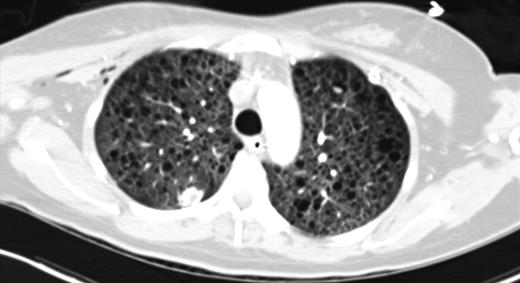

Since discharge from our institution, the patient remains independent of oxygen supplementation. Due to a severe perturbation in her diffusing capacity of the lung for carbon monoxide (DLCO), she was started on sirolimus, a treatment for LAM. Her most recent pulmonary function testing (PFT) revealed a DLCO of 41% predicted and a 6-min walk culminated in desaturation from baseline pulse oximetry of 98–80%. A representative section from her most recent chest CT, performed 8 months after discharge, is shown in Fig. 3.

CT chest (axial slices in lung window) demonstrating interval resolution of pneumothoraces and persistent, diffuse numerous thin-walled pulmonary cysts without cardiophrenic sparing.